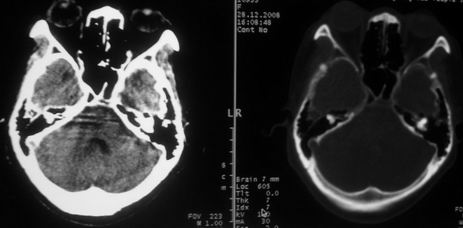

女,72岁,头晕。额骨有无问题。

额骨呈磨玻璃状增厚,考虑骨纤。

额骨呈磨玻璃状增厚,考虑骨纤

骨纤维组织异常增殖症又名纤维性骨炎,是一种以骨纤维变性为特点的骨胳系统疾病,是否为一真性肿瘤尚无定论。该病好友于儿童及青年,女性较多见,60%发生于20岁以前,偶见于婴儿和70岁以上老年人。男女发病为1∶2。80%以上表现为病骨区畸形肿胀;建议祥问病史,时间?